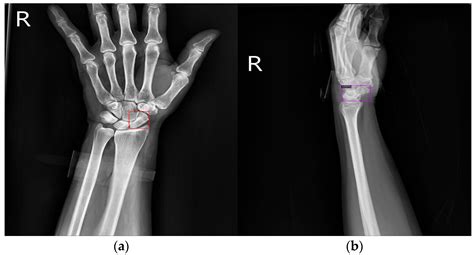

• Imaging Studies: X-rays are the most common imaging tool used to diagnose non displaced fractures. They can provide a clear view of the bone and help determine the location and extent of the fracture. In some cases, additional imaging studies such as CT scans or MRI may be necessary to get a more detailed view of the injury.